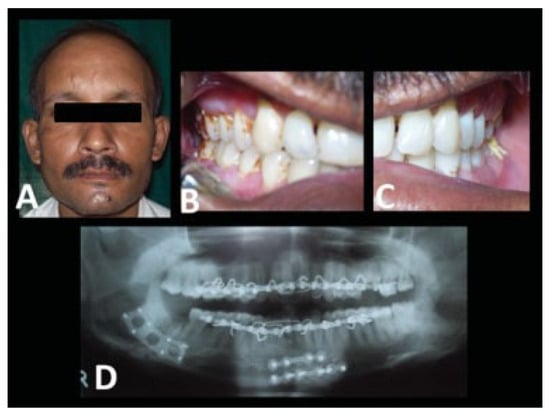

| Case no. | Age | Sex | Etiology | Fractured sites |

| 1 | 25 | M | RTA | Rt. parasymphysis and Lt. angle |

| 2 | 22 | M | RTA | Lt. angle |

| 3 | 20 | M | RTA | Rt. parasymphysis and Lt. angle |

| 4 | 22 | M | Assault | Lt. angle |

| 5 | 25 | M | RTA | Lt. angle |

| 6 | 23 | M | RTA | Lt. body and Rt. angle |

| 7 | 27 | M | RTA | Lt. angle |

| 8 | 25 | M | Industrial | Lt. parasymphysis and Rt. angle |

| 9 | 32 | M | Fall | Lt. parasymphysis and Rt. angle |

| 10 | 27 | M | RTA | Rt. angle |

| 11 | 24 | M | RTA | Rt. angle |

| 12 | 38 | F | Fall | Lt. angle |

| 13 | 21 | M | RTA | Rt. parasymphysis and Lt. angle |

| 14 | 33 | M | RTA | B/l angle |

| 15 | 40 | M | RTA | Lt. parasymphysis and Rt. angle |

| 16 | 33 | M | RTA | Rt. parasymphysis and Lt. angle |

| 17 | 31 | M | RTA | Lt. angle |

| 18 | 50 | M | RTA | Lt. angle |

| 19 | 26 | F | Fall | Rt. angle |

| 20 | 32 | M | Assault | Lt. parasymphysis and Rt. angle |